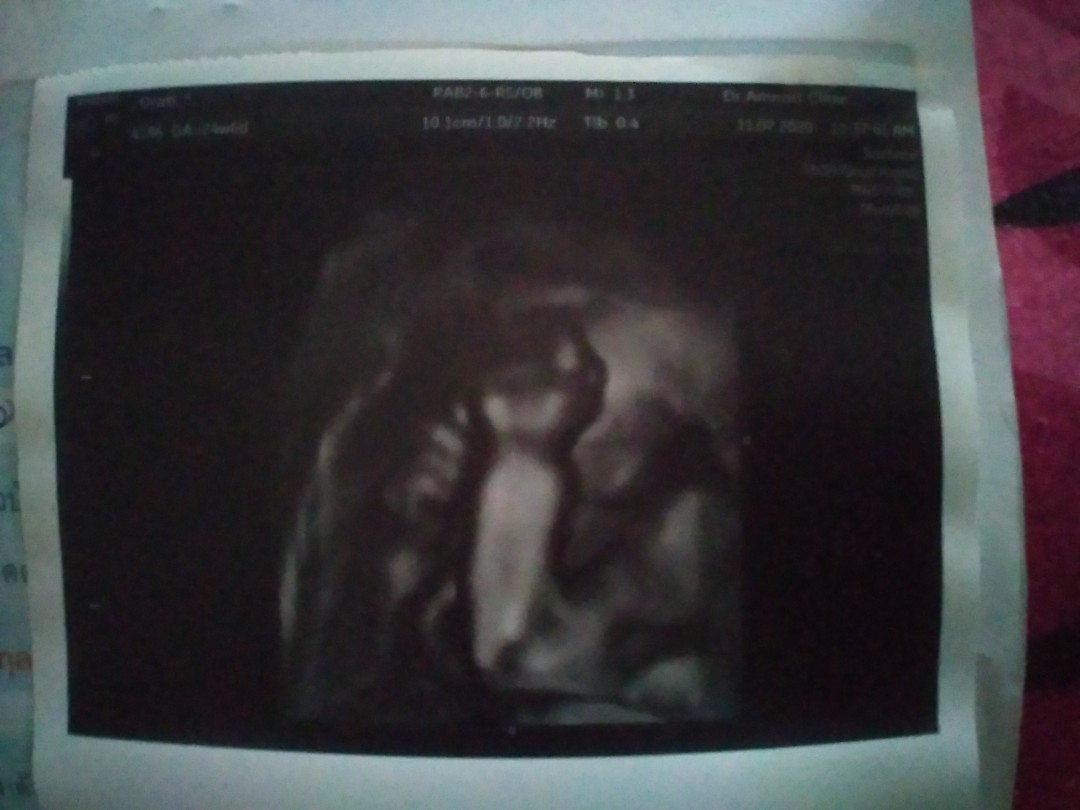

ตอน10วีค6วันค่ะ

9วีค2วันคะ

ตอน 10w+1d คะ

10+1 วีคค่ะ